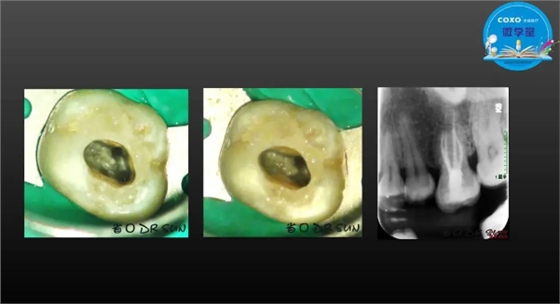

主讲:孙书昱

主任医师,牙体牙髓副主任, 广东省口腔医院牙体牙髓科 主任医师。2003年硕士研究生毕业,研究方向为牙体牙髓病学,擅长于牙体牙髓病的诊断、龋齿、牙髓炎、根尖周病的治疗以及前牙美容修复。